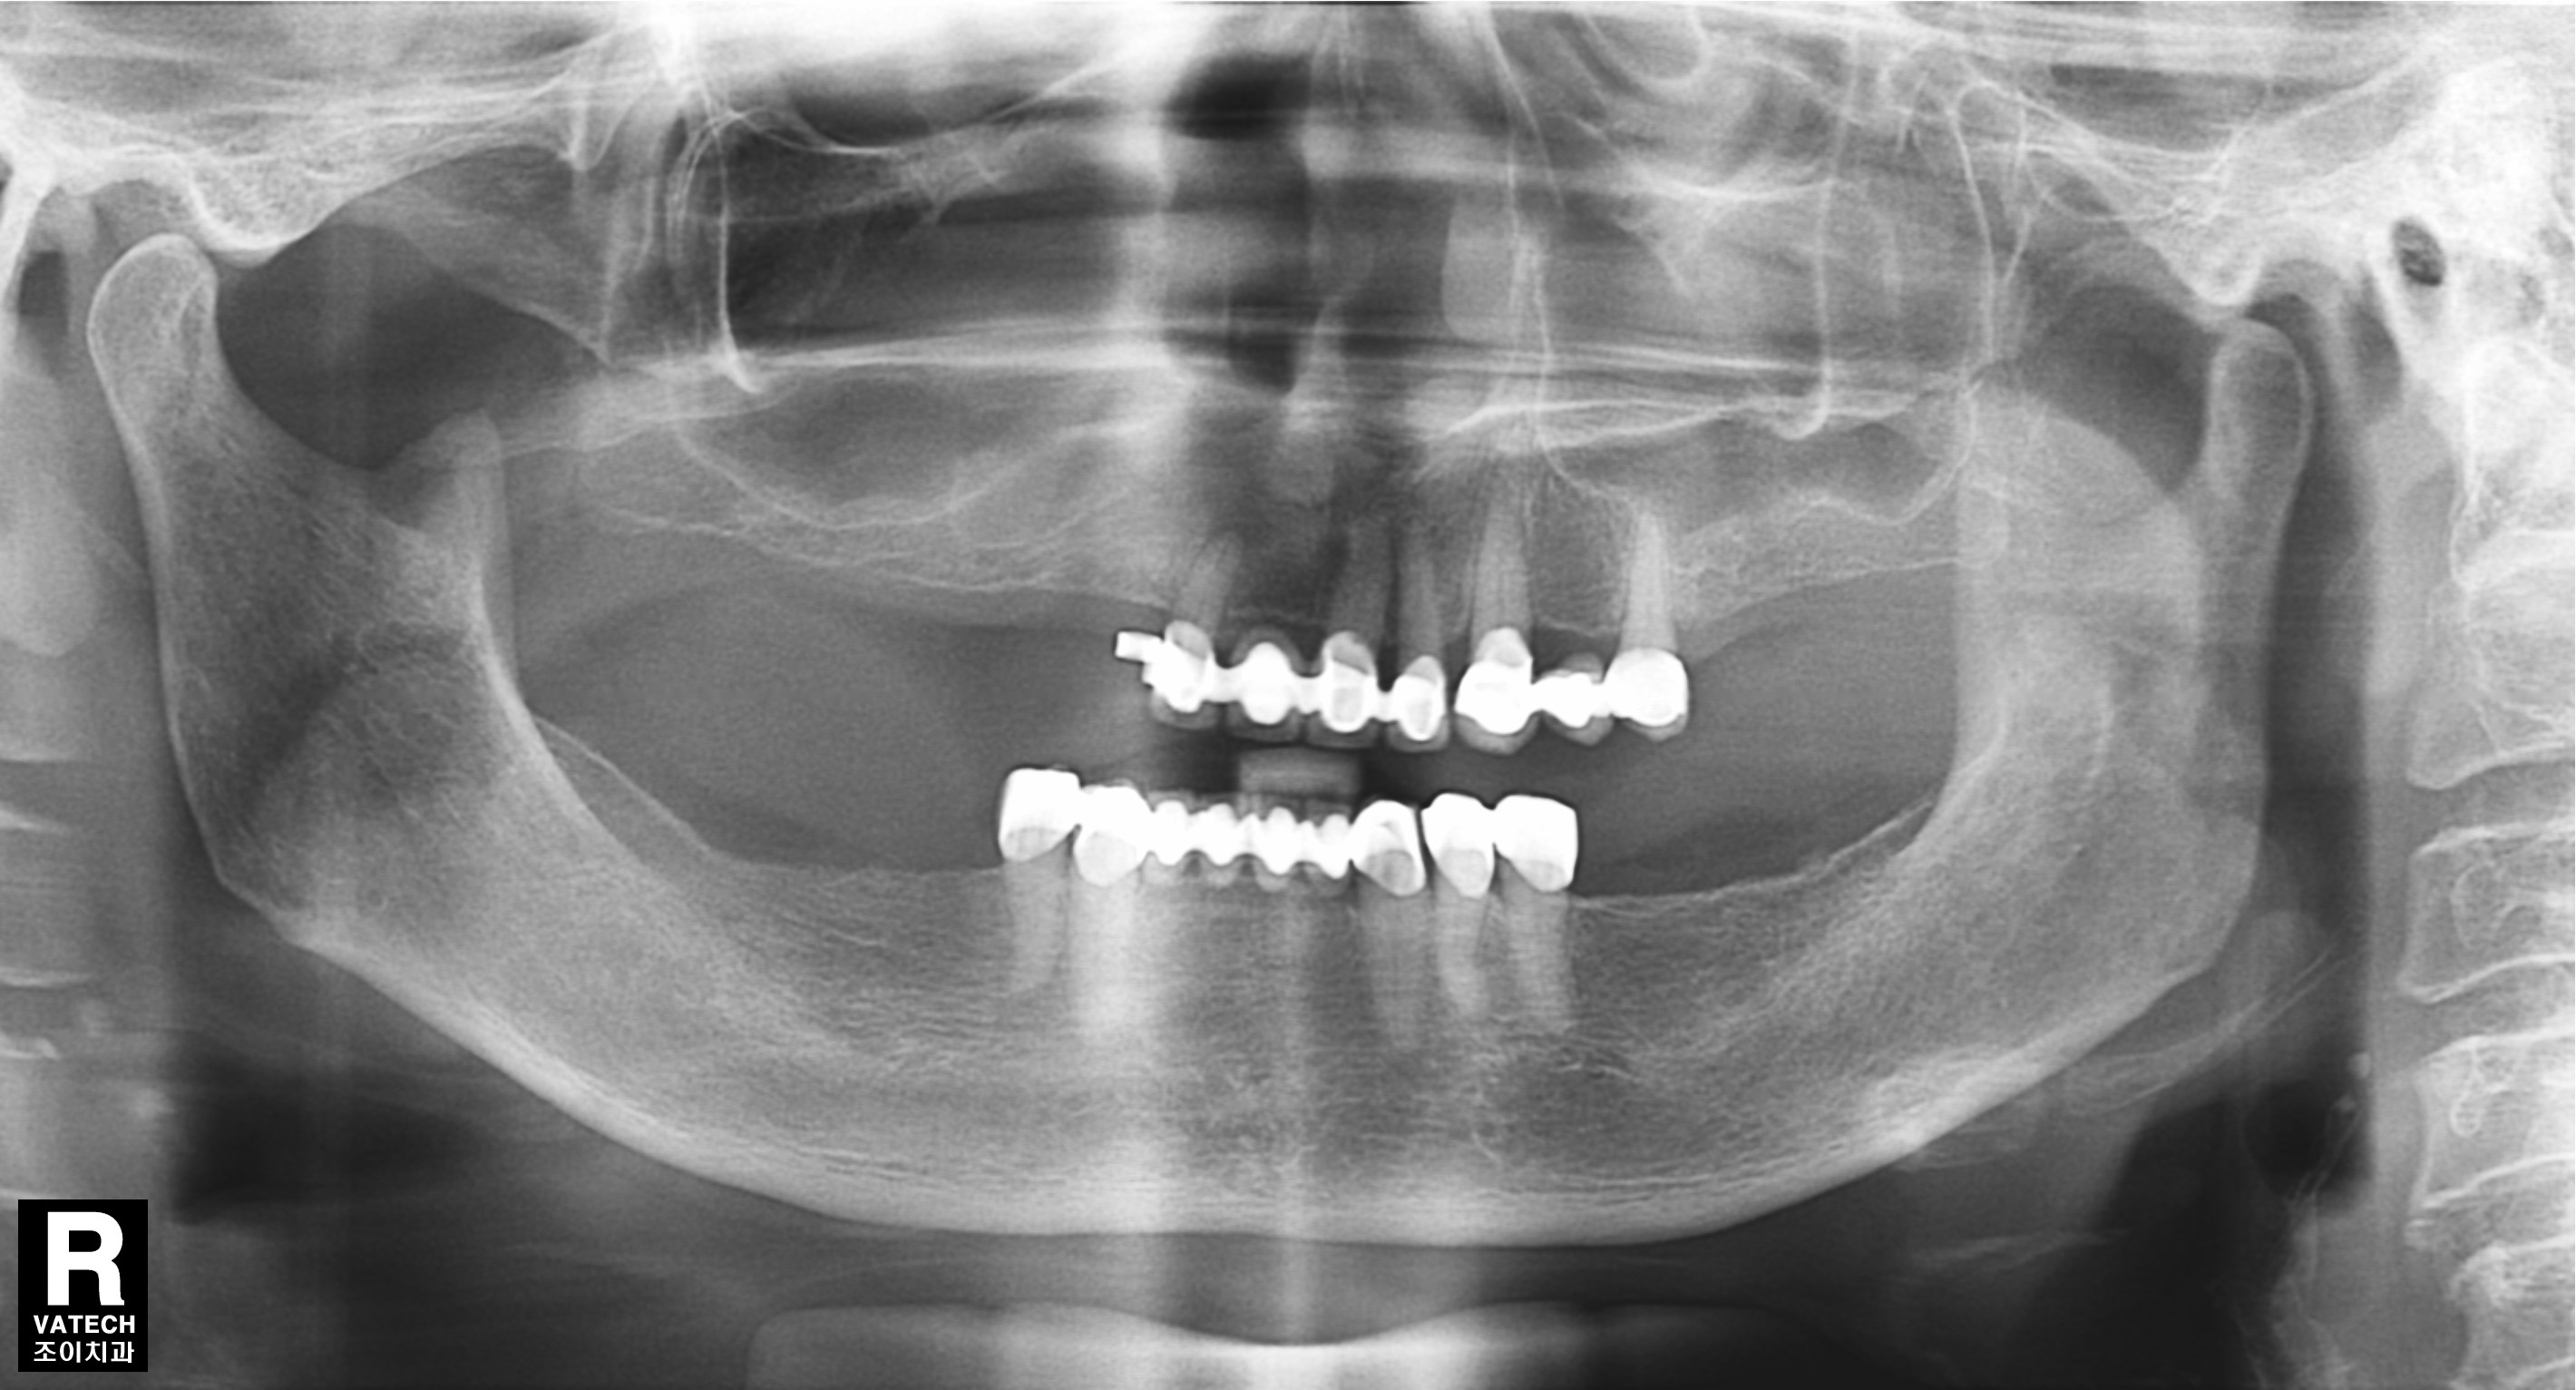

[임플란트] 제목 : 부분틀니 벗기

라식해서 안경을 벗듯이, 임플란트해서 틀니를 벗은 경우입니다.

요즘은 임플란트가 있으니 야예 틀니를 하지 않는 것이 더 좋은 방법일 듯 합니다.